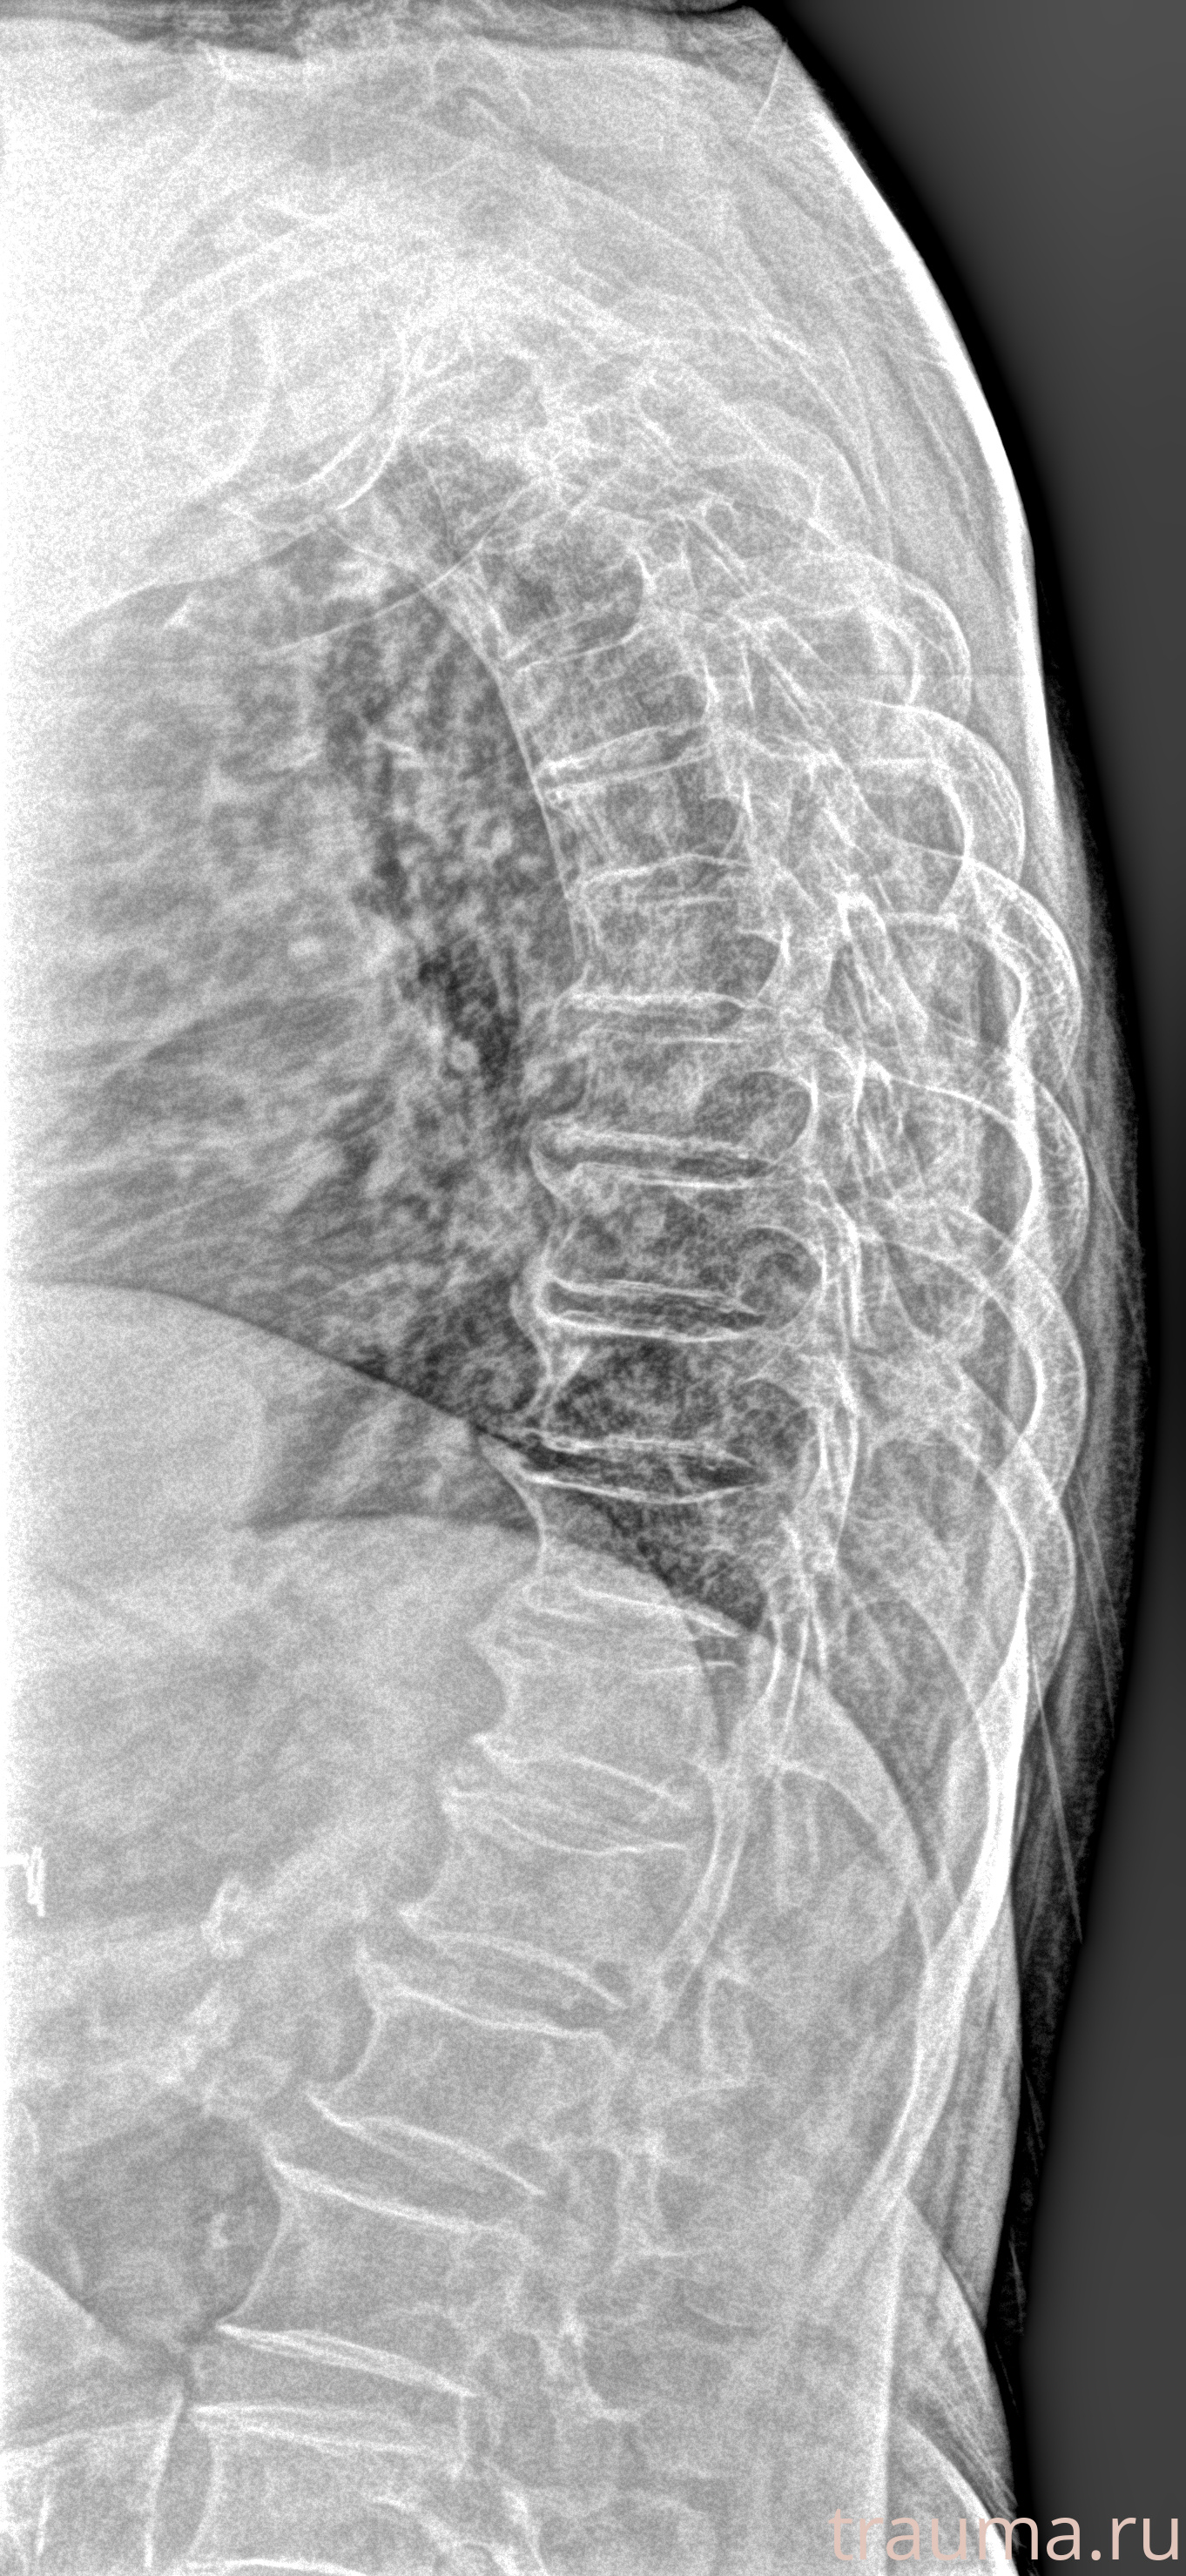

Рентген на дому: по вашему адресу приезжает врач-рентгенолог, травматолог-ортопед с мобильным рентгеновским аппаратом, проводит диагностику травмы или заболевания, делает необходимые рентгенограммы, дает рекомендации по дальнейшему лечению. Получить качественные снимки в домашних условиях возможно благодаря уникальной методике, разработанной МосРентген Центром для института  Склифосовского